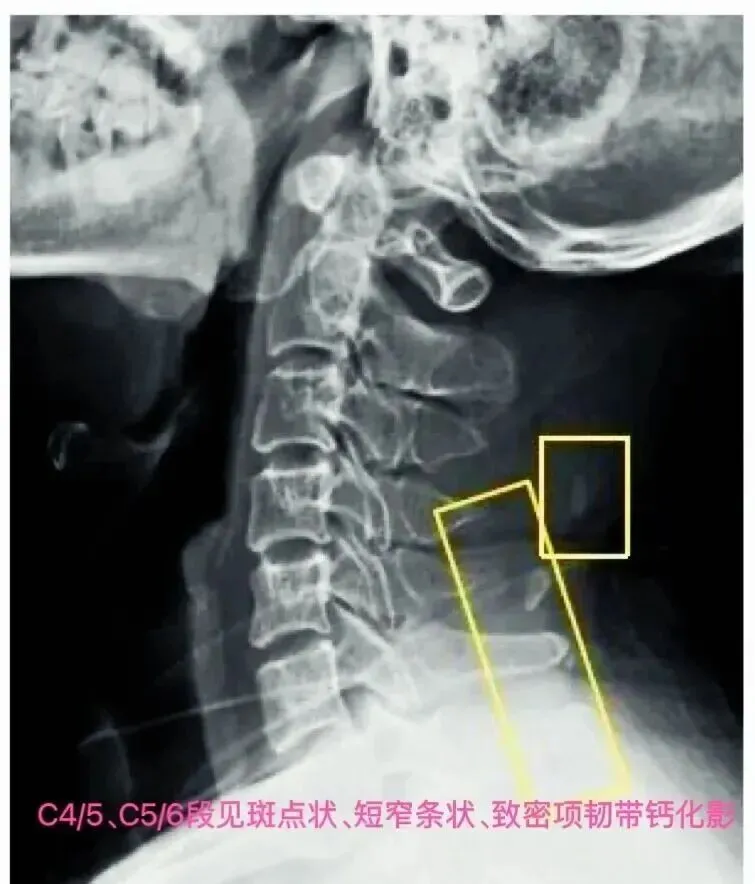

(二)侧位片观察要点

示例